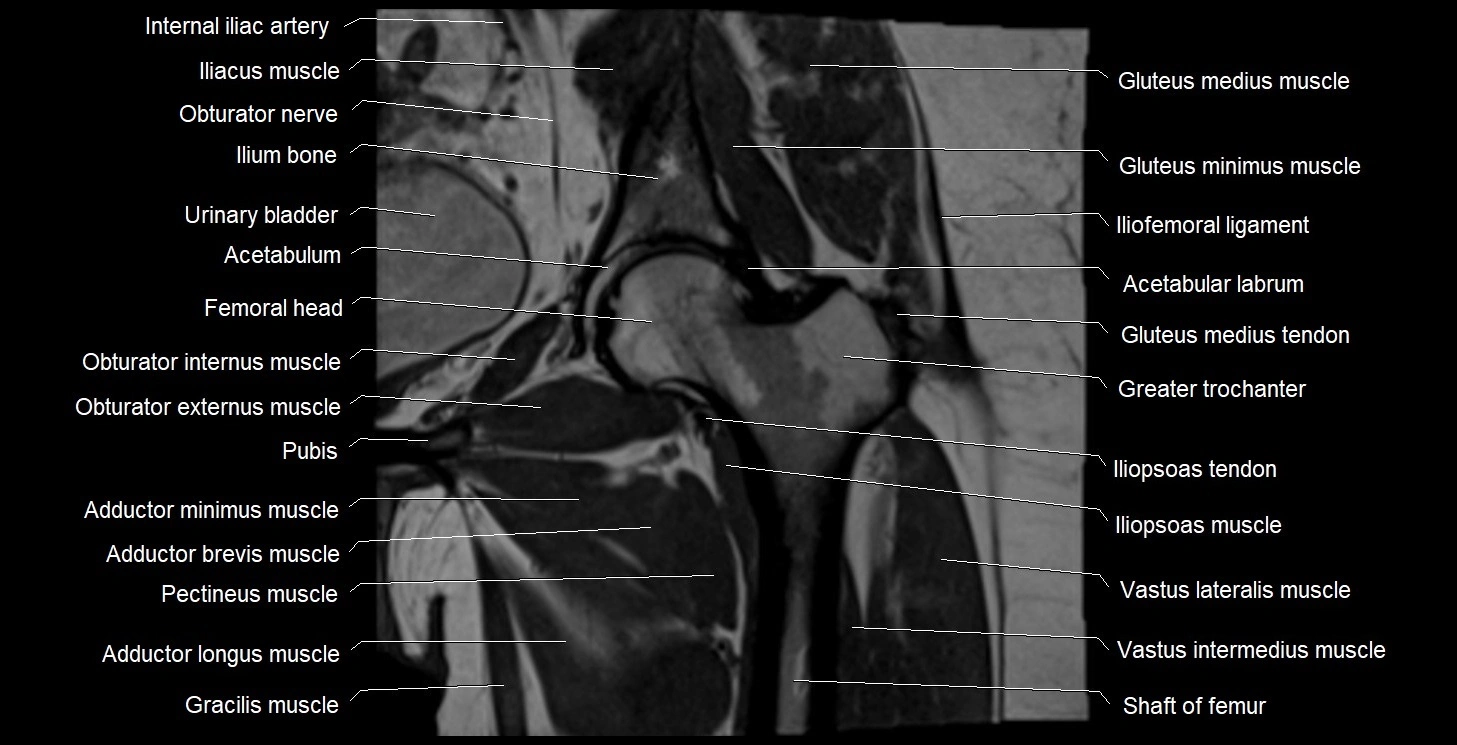

- Acetabulum

- Head of femur

- Hip joint

- Iliopsoas muscle

- Iliopsoas tendon

- Ilium bone

- Obturator externus muscle

- Obturator internus muscle

- Obturator nerve

- Pectineus muscle

- Vastus intermedius muscle

- Vastus lateralis muscle